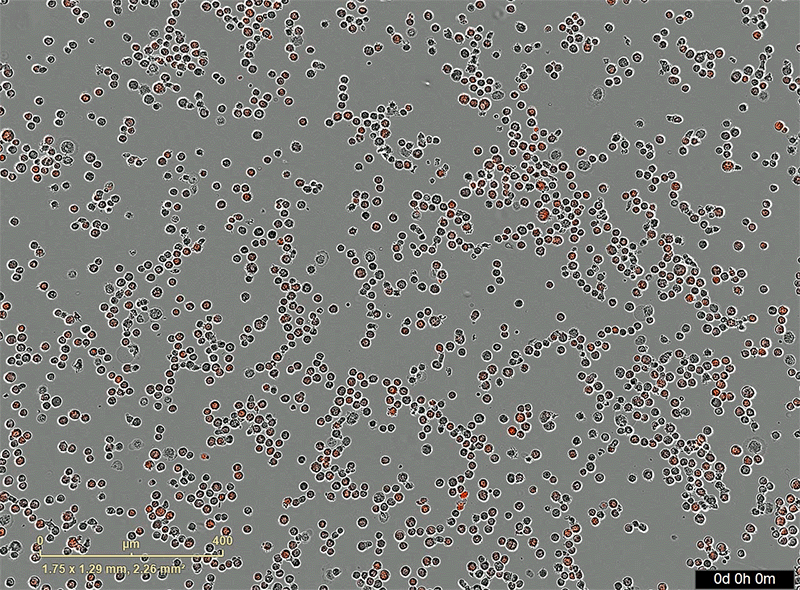

Animation shows, over 5 hours, red dots indicating killed cancer cells.

Caption: This animation of AbLec-treated macrophages and cancer cells show how cancer cell killing happens over a period of 5 hours. The red fluorescence indicates cancer cells that have been killed by the macrophages.

This animation of AbLec-treated macrophages and cancer cells show how cancer cell killing happens over a period of 5 hours. The red fluorescence indicates cancer cells that have been killed by the macrophages.